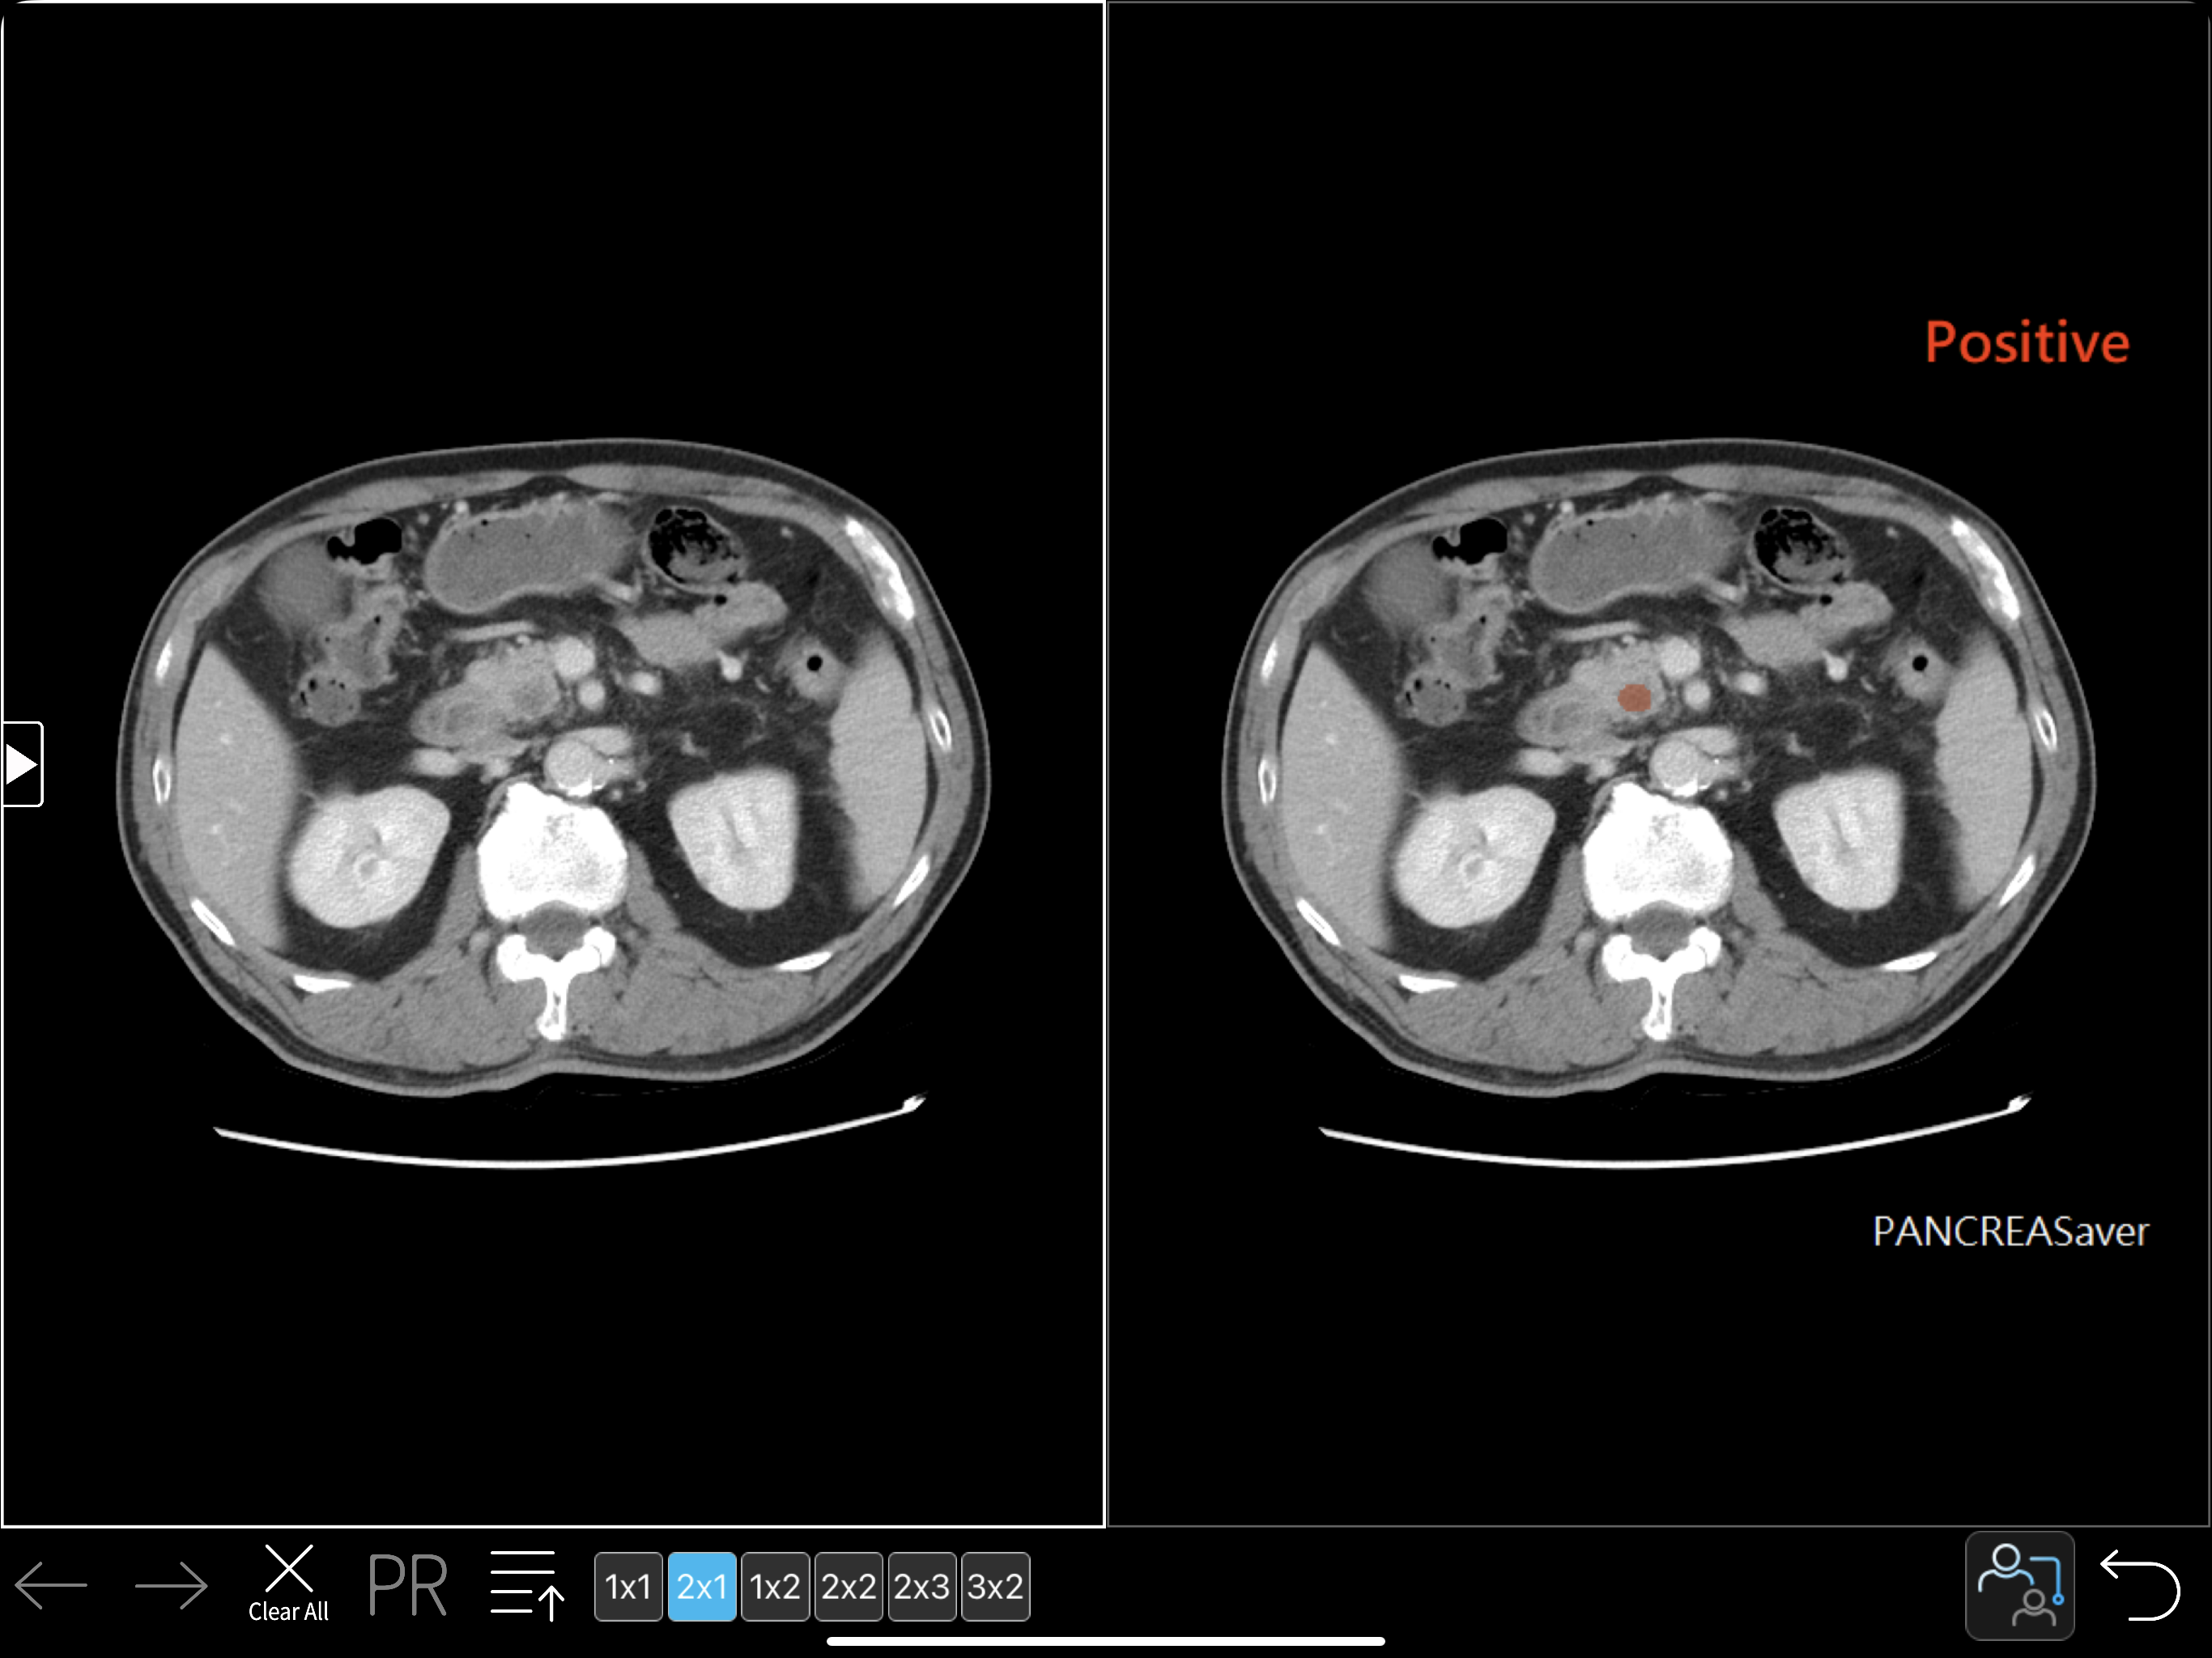

PANCREASaver is an automatic end-to-end tool which determines whether CT images harbor PC.

PANCREASaver identifies missed pancreatic cancer, accurately differentiates subjects with or without pancreatic cancer on CT, and indicates the location of the tumor without requiring manual image labeling or preprocessing.